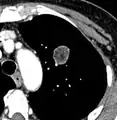

- In case of calcifications, a popcorn-like appearance indicates a hamartoma, which is benign.[3]

- Areas of fatty tissue (−40 to −120 HU) indicates a hamartoma. However, only about 50% of hamartomas are fat containing.[9]

Low attenuating nodule (in this case a fat containing hamartoma).[9]